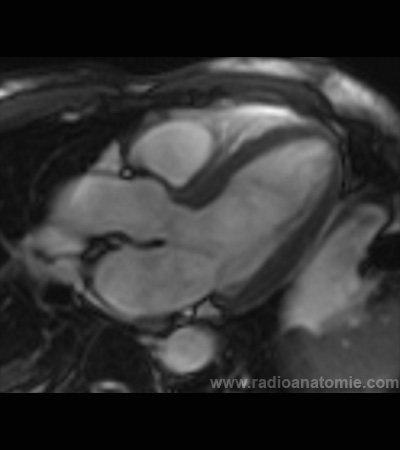

Radioanatomie et plans de coupe en IRM cardiaque